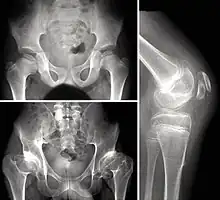

Children with autosomal dominant MED experience joint pain and fatigue after exercising. Their x-rays show small and irregular ossification centers, most apparent in the hips and knees. There are very small capital femoral epiphyses and hypoplastic, poorly formed acetabular roofs.[1] A waddling gait may develop. Knees have metaphyseal widening and irregularity while hands have brachydactyly (short fingers) and proximal metacarpal rounding. Flat feet are very common.[2] The spine is normal but may have a few irregularities, such as scoliosis.

By adulthood, people with MED are of short stature or in the low range of normal and have short limbs relative to their trunks. Frequently, movement becomes limited at the major joints, especially at the elbows and hips. However, loose knee and finger joints can occur. Signs of osteoarthritis usually begin in early adulthood.[3]

Children with recessive MED experience joint pain, particularly of the hips and knees, and commonly have deformities of the hands, feet, knees, or vertebral column (like scoliosis). Approximately 50% of affected children have abnormal findings at birth (such as club foot or twisted metatarsals, cleft palate, inward curving fingers due to underdeveloped bones and brachydactyly, or ear swelling caused by injury during birth). Height is in the normal range before puberty. As adults, people with recessive MED are only slightly more diminished in stature, but within the normal range. Lateral knee radiography can show multi-layered patellae.[3]